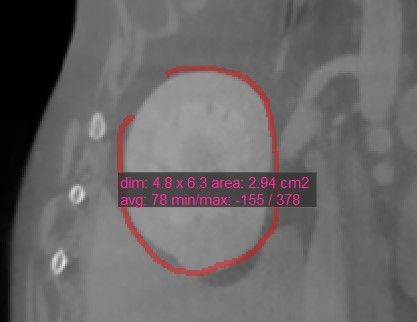

Polygon¶

Benutzer können mit dem Werkzeug Polygon benutzerdefinierte, abgerundete Bereiche auf der aktiven Bildschicht erstellen, messen und markieren.

Wählen Sie das Werkzeug Polygon aus und weisen Sie es einer der verfügbaren Maustasten zu. Starten Sie die Messung, indem Sie Punkte auf der aktiven Bildschicht setzen. Während der Benutzer die Punkte setzt, verbindet die Software sie automatisch und erstellt die abgerundete Form.

Schließen Sie die Messung, indem Sie den Pfad manuell schließen, oder doppelklicken Sie beim Setzen des letzten Punkts, um ihn automatisch zu schließen. Alle verfügbaren Messwerte werden zusammen mit der Messung angezeigt.

Ändern Sie den markierten Bereich, indem Sie einen der Punkte, die die Form beschreiben, mit dem Werkzeug Standard verschieben.